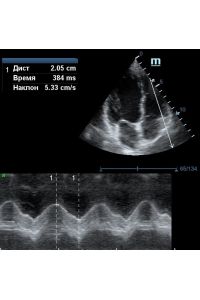

Оценка кооптации нижней полой вены ещё никогда не была такой простой и точной, никаких лишних деталей, просто устанавливаем клипер по анэхогенному участку.